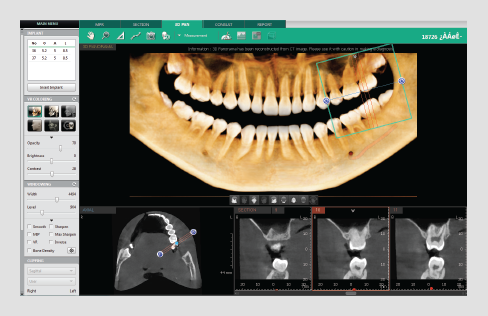

• 3D panorama

• 3D panorama

• Easily navigate and obtain a sectional view by utilizing our new and intuitive 3D panoramic navigation mode

• Simply click and drag our viewing window over the 3D panorama to obtain a sectional view of that region

• Angulation made easy

By clicking 3D Navigator and positioning to ROI,

it’s easy to verify 2D sectional images.

• Available in all viewing modes in the Ez3D-i (MPR/Section/3DPan)

SECTION TAB

3D PAN TAB

• Draw sectional curves from either the MPR View or Sectional View

• Easily manage up to 8 different sectional curves

• Intuitive click-and-drag sectional view manipulation